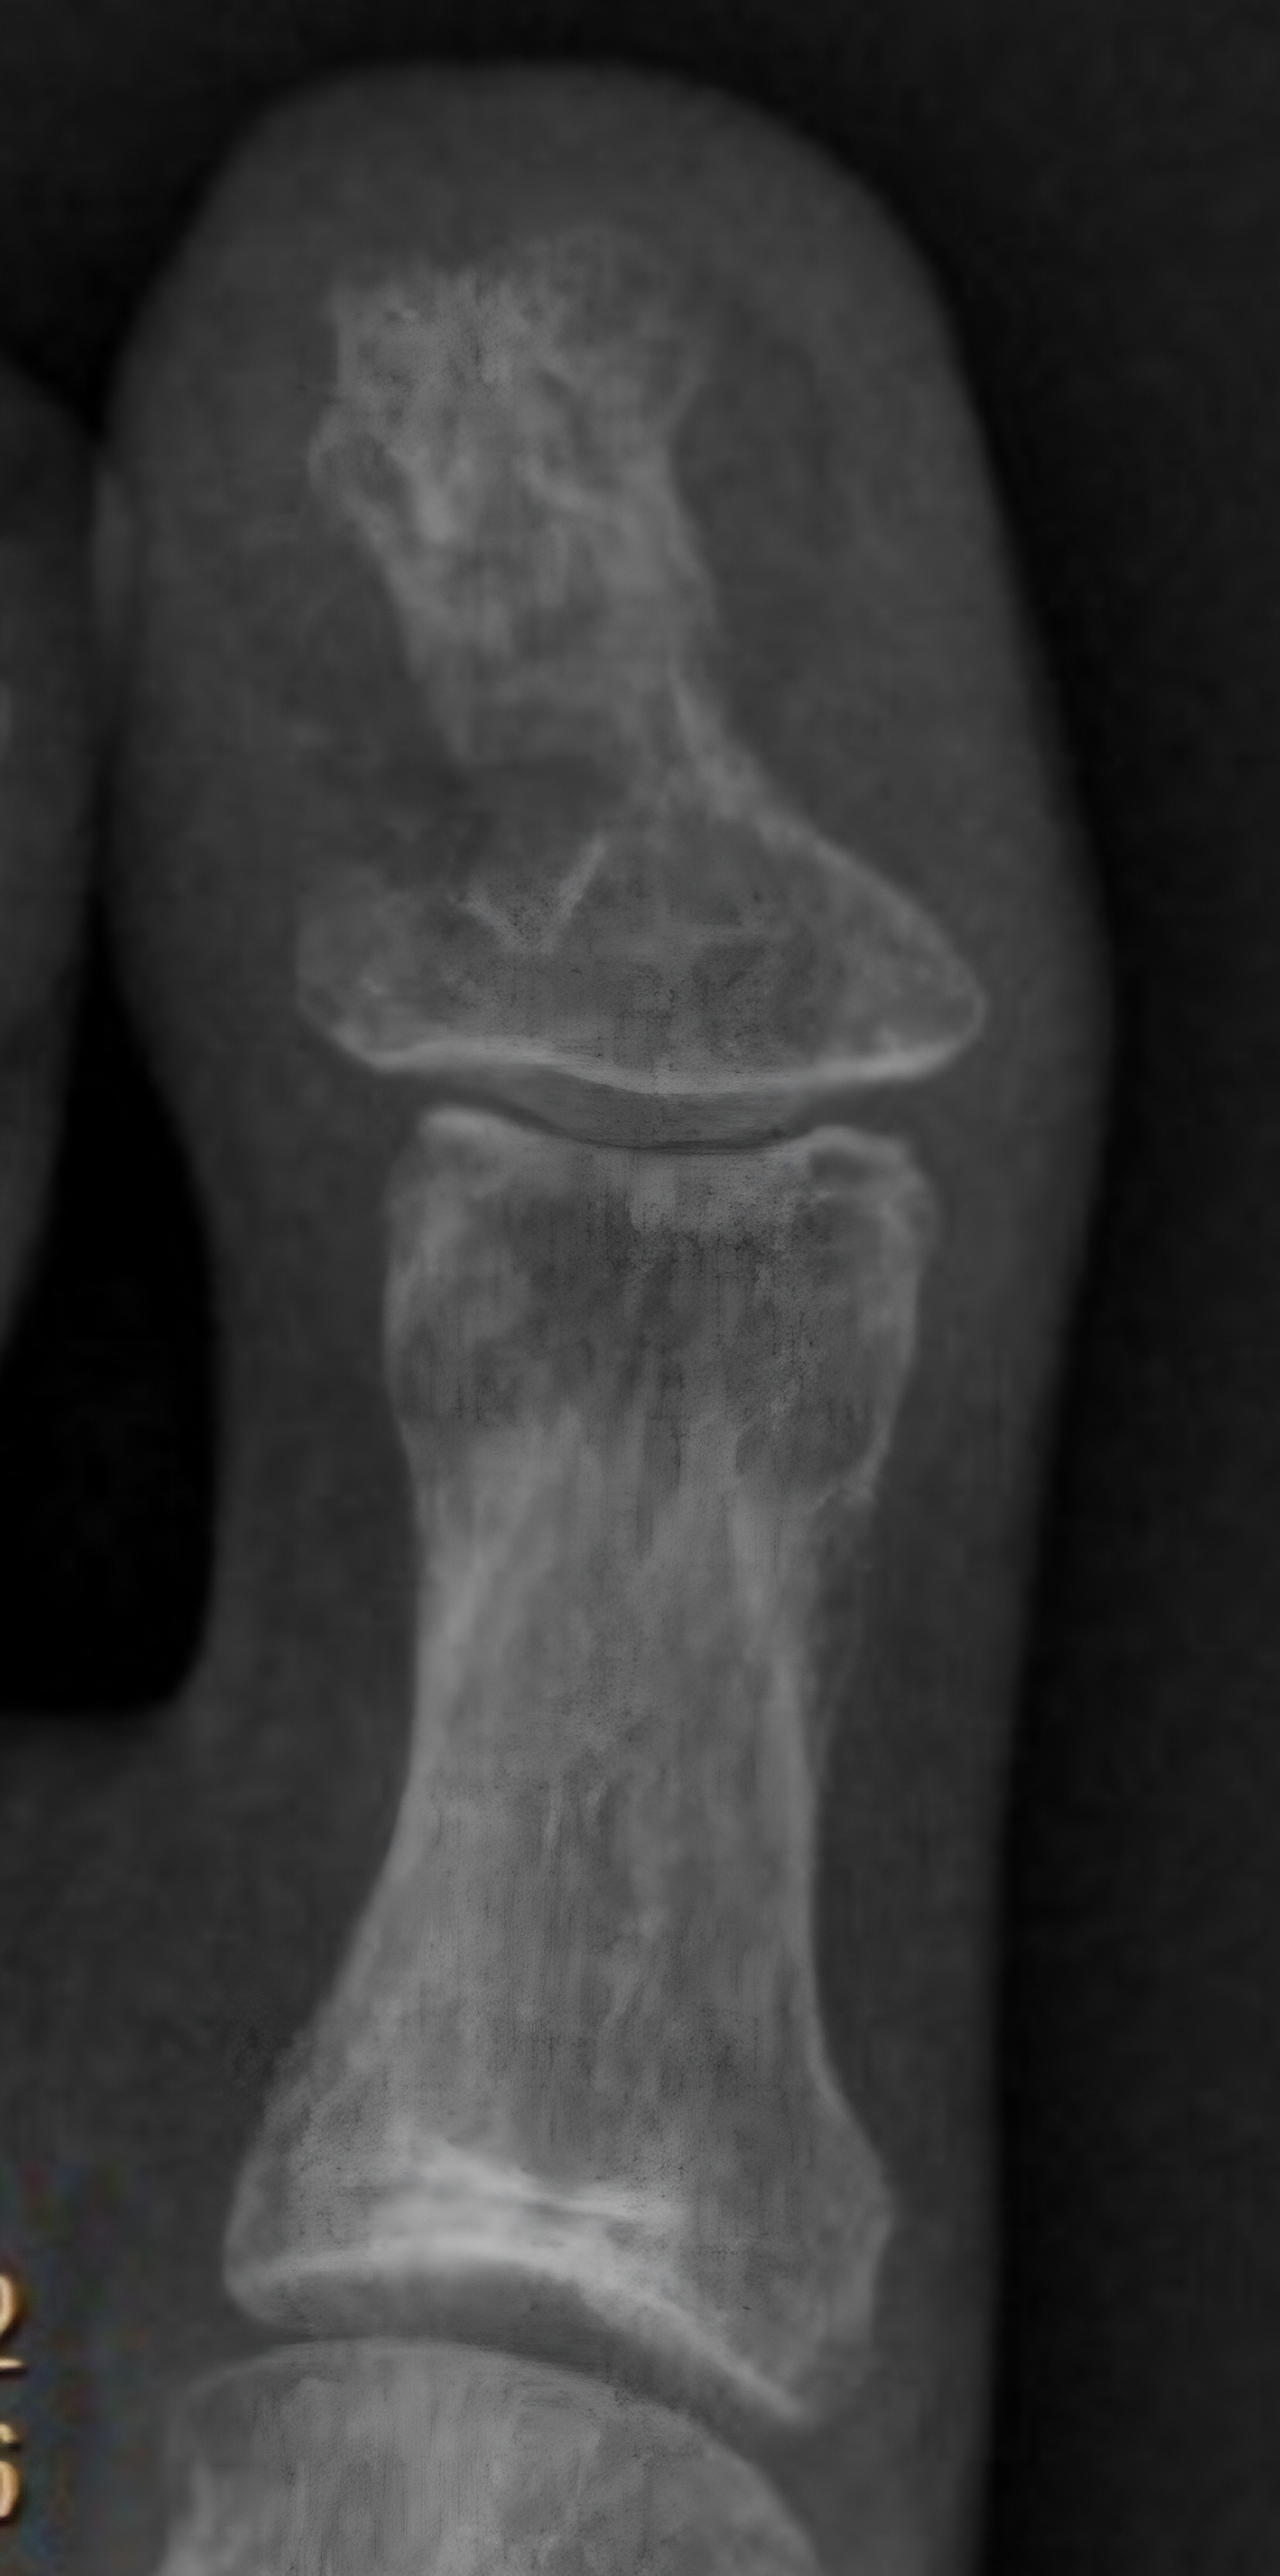

Patient was hospitalized in August 2022 for IV (Intravenous) metronidazole which helped reduce (but not eliminate) symptoms for about one month. MRI of the left toe showed still healing fracture and ortho consult did not recommend surgical intervention at that time. Multiple neurology consults were obtained to rule out neurological cause of symptoms given the unusual presentation and all neurology consults felt this was not primarily a neurological issue and she was referred back to Infectious Disease for management. EMG & MRI of the brain were done and were both normal. (Patient was advised to continue benzodiazepine during initial EMG so any possible exaggerated F-response and spasms were suppressed by benzodiazepines during the EMG). During all physical exams involuntary muscle spasms/ twitching of the left foot/toes were noted involving both agonist and antagonist muscles.

MRI one year after injury showed some abnormal signal. (Clostridium tetani infection generally has no clear radiological findings or lab confirmatory tests and is generally a clinical diagnosis). Patient sought consults with multiple infectious disease doctors in New York but despite repeated worsening off antibiotics, clear clinical signs of local tetanus in the left foot, progression of spasms / twitching up the left leg with generalization and autonomic symptoms including heart block and involuntary jaw closure within days of stopping antibiotics or walking more than small amounts, infectious disease physicians in New York (who have not had experience with tetanus) have been conflicted on the diagnosis and of little help. (The medical literature reports that the presentation of tetanus in an immunized patient would typically be different than the presentation in an unimmunized patient and instead of presenting with full body tetany, an immunized patient would present with an ascending pattern of spasms / twitching up the affected limb from the localized point of infection with progression to generalization as in this case.)

Patient sought surgical consult with a bone specialist surgeon who diagnosed patient clinically with tetanus osteomyelitis & surgical debridement of the left big toe (distal bone) was attempted 2 times. First surgery involved bone debridement of the medial side of the toe with placement of antibiotic laden calcium stimulan beads. The first surgery did not resolve the symptoms and actually worsened tetanus symptoms for about a month post surgery. One episode of brief full left leg tetany occurred in the first month post surgery . During the surgery, the surgeon visually graded the bone as "infected" with an infection level of 4 out of 4, stating the bone appeared much softer than it should be. (The surgeon specializes in bone surgery and stated he had never seen bone that looked like this) Cultures (anaerobic, aerobic and fungal) were negative but the surgeon and literature advises that anaerobic cultures rarely come back positive (accuracy is only about 30% in confirmed positive cases).